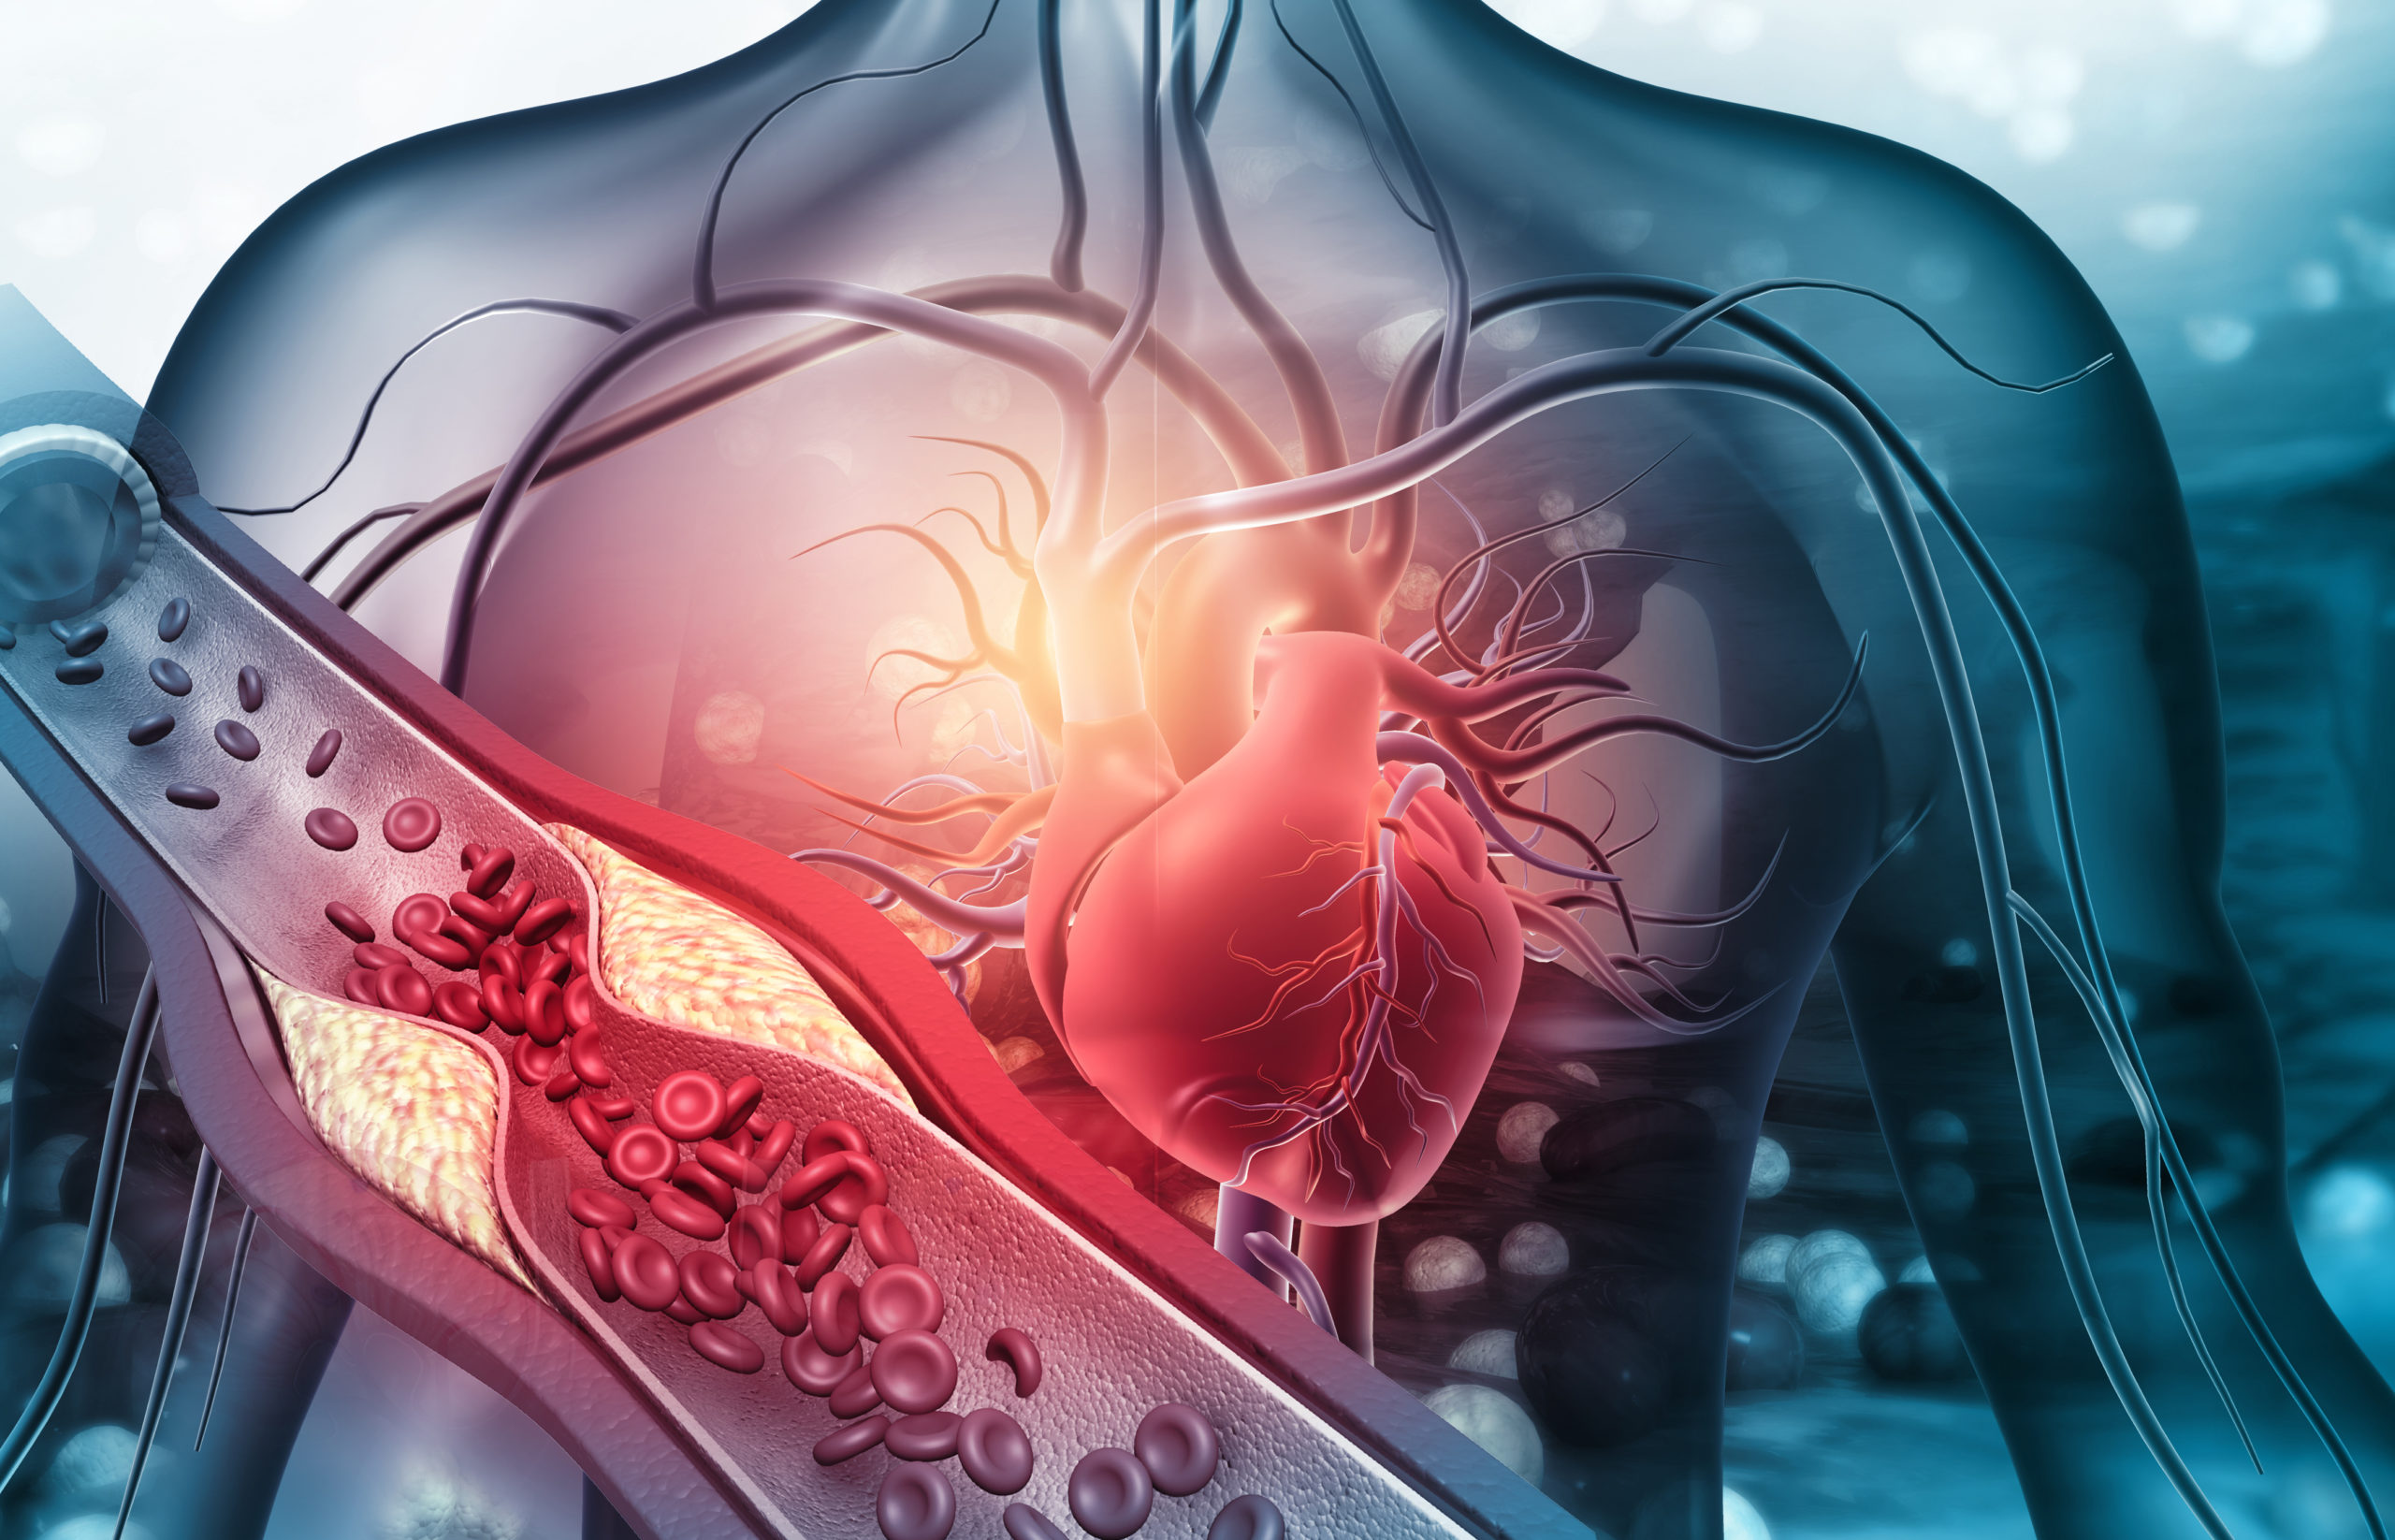

Peripheral artery disease (PAD) is a significant contributor in cardiovascular morbidity and mortality; However, ...

Researchers assessed the predictive value of post-systolic shortening (PSS) for early identification of myocardial ...

Investigators have found that night shift workers are significantly more likely to develop atrial fibrillation (AF) and ...

There exists a correlation between high body mass index (BMI), and peripheral artery disease (PAD), according to a ...